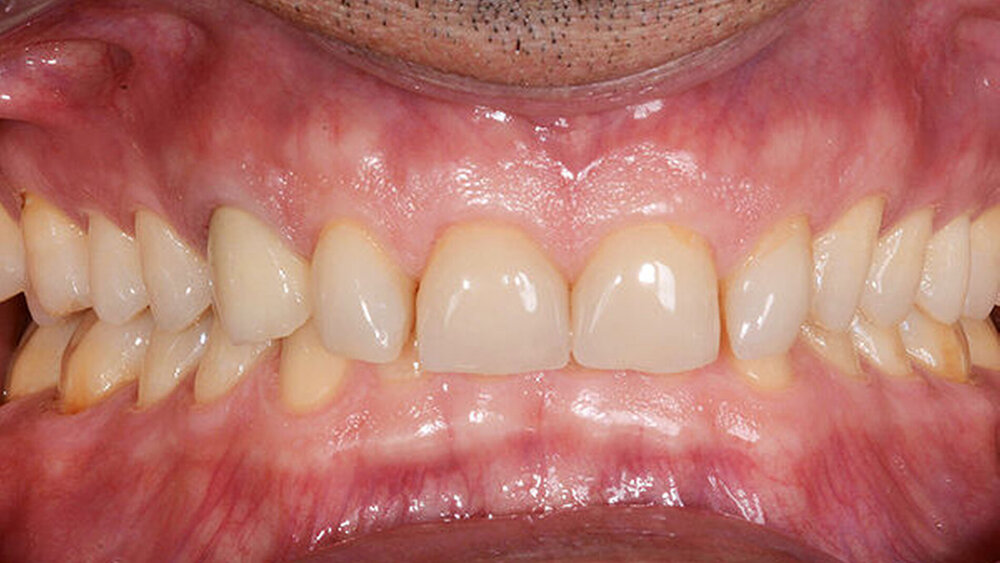

Die Kronen (11–13, 21–23) und Veneers (14, 15, 16, 17, 24, 25, 26, 27, 31, 32, 33, 34, 35, 36, 37, 41, 42, 43, 44, 45, 46, 47) wurden mit einem lichthärtenden, polymerisierenden Harz‧adhäsiv (Futurabond U und Bifix QM; VOCO) an den Abutments befestigt. Zur Polymerisation wurde ein Hochleistungs-LED-Lichthärtegerät verwendet (Celalux 3; VOCO), siehe die Abbildungen 11 und 12.

Überschüssiges Befestigungsmaterial wurde entfernt und Anpassungen der Okklusion wurden vorgenommen und mit der T-Scan-Technologie (TeK-scan) überprüft. Zum Schutz der endgültigen Restaurationen wurde eine abnehmbare Acrylschiene angefertigt. Nach 6 Monaten wurden die endgültigen Restaurationen überprüft. Sie waren noch immer stabil und wiesen keine Frakturspuren auf (Abb. 13–15). Der Patient berichtete zudem, dass er mit der neuen Bisshöhe keine Kopfschmerzen mehr hatte.